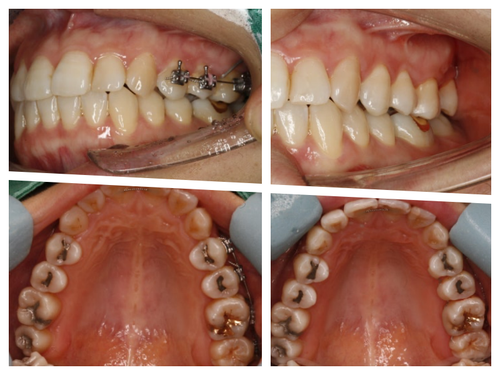

공교롭게도 이 환자도 27세 여성환자...

늘 열심히 일하고 야간진료 때 컴퓨터 가방을 들고 오던 환자였다.

일도 힘들었을텐데 꼬박 꼬박 진료도 잘 와줘서 사랑니가 원래 제 자리였던것처럼 위치하고 있다.

비용도 수고로움도 임플란트만큼이지만 치주인대를 갖고있는 나의 치아로 대체할 수 있음은 충분히 투자가치가 있다는 개인적인 의견이다...